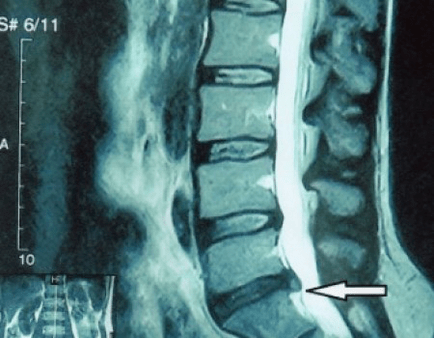

Kuna kettaid endid saab näha ainult CT või MRI abil, on kõhre ja moodustiste, nagu eendid ja herniad, sisemise struktuuri selgitamiseks ette nähtud magnetresonants- ja röntgen-kompuutertomograafia. Seega tehakse nende meetodite abil täpselt diagnoos ning tomograafia tulemus on näidustus ja isegi aktuaalne juhend hernia kirurgiliseks raviks neurokirurgia osakonnas.

- kui teil on song, peate seda dünaamiliselt jälgima, tegema regulaarseid MRI-sid, vältima selle suuruse suurendamist või läbi viima kaasaegse minimaalselt invasiivse kirurgilise ravi, kuna eranditult kõik osteokondroosi ägenemise konservatiivsed meetodid jätavad songa paigale ja kõrvaldavad ainult ajutised sümptomid: põletik, valu, tulistamine ja lihasspasmid.

Soovitav on, et iga patsient pärast sümptomite progresseerumist ja tüsistuste esinemist läbiks MRI ja pöörduks neurokirurgi poole. Kaasaegsed minimaalselt invasiivsed operatsioonid võimaldavad ohutult eemaldada üsna suuri songasid ilma pikema haiglaravita, ilma, et oleks sunnitud mitu päeva pikali jääma, ilma elukvaliteeti kahjustamata, kuna need tehakse kaasaegse videoendoskoopilise, raadiosagedusliku, lasertehnoloogia või külma plasma abil. Saate osa tuumast aurustada ja rõhku alandada, vähendades sellega hernia saamise ohtu. Ja saate defekti radikaalselt kõrvaldada, see tähendab, et sellest täielikult vabaneda.